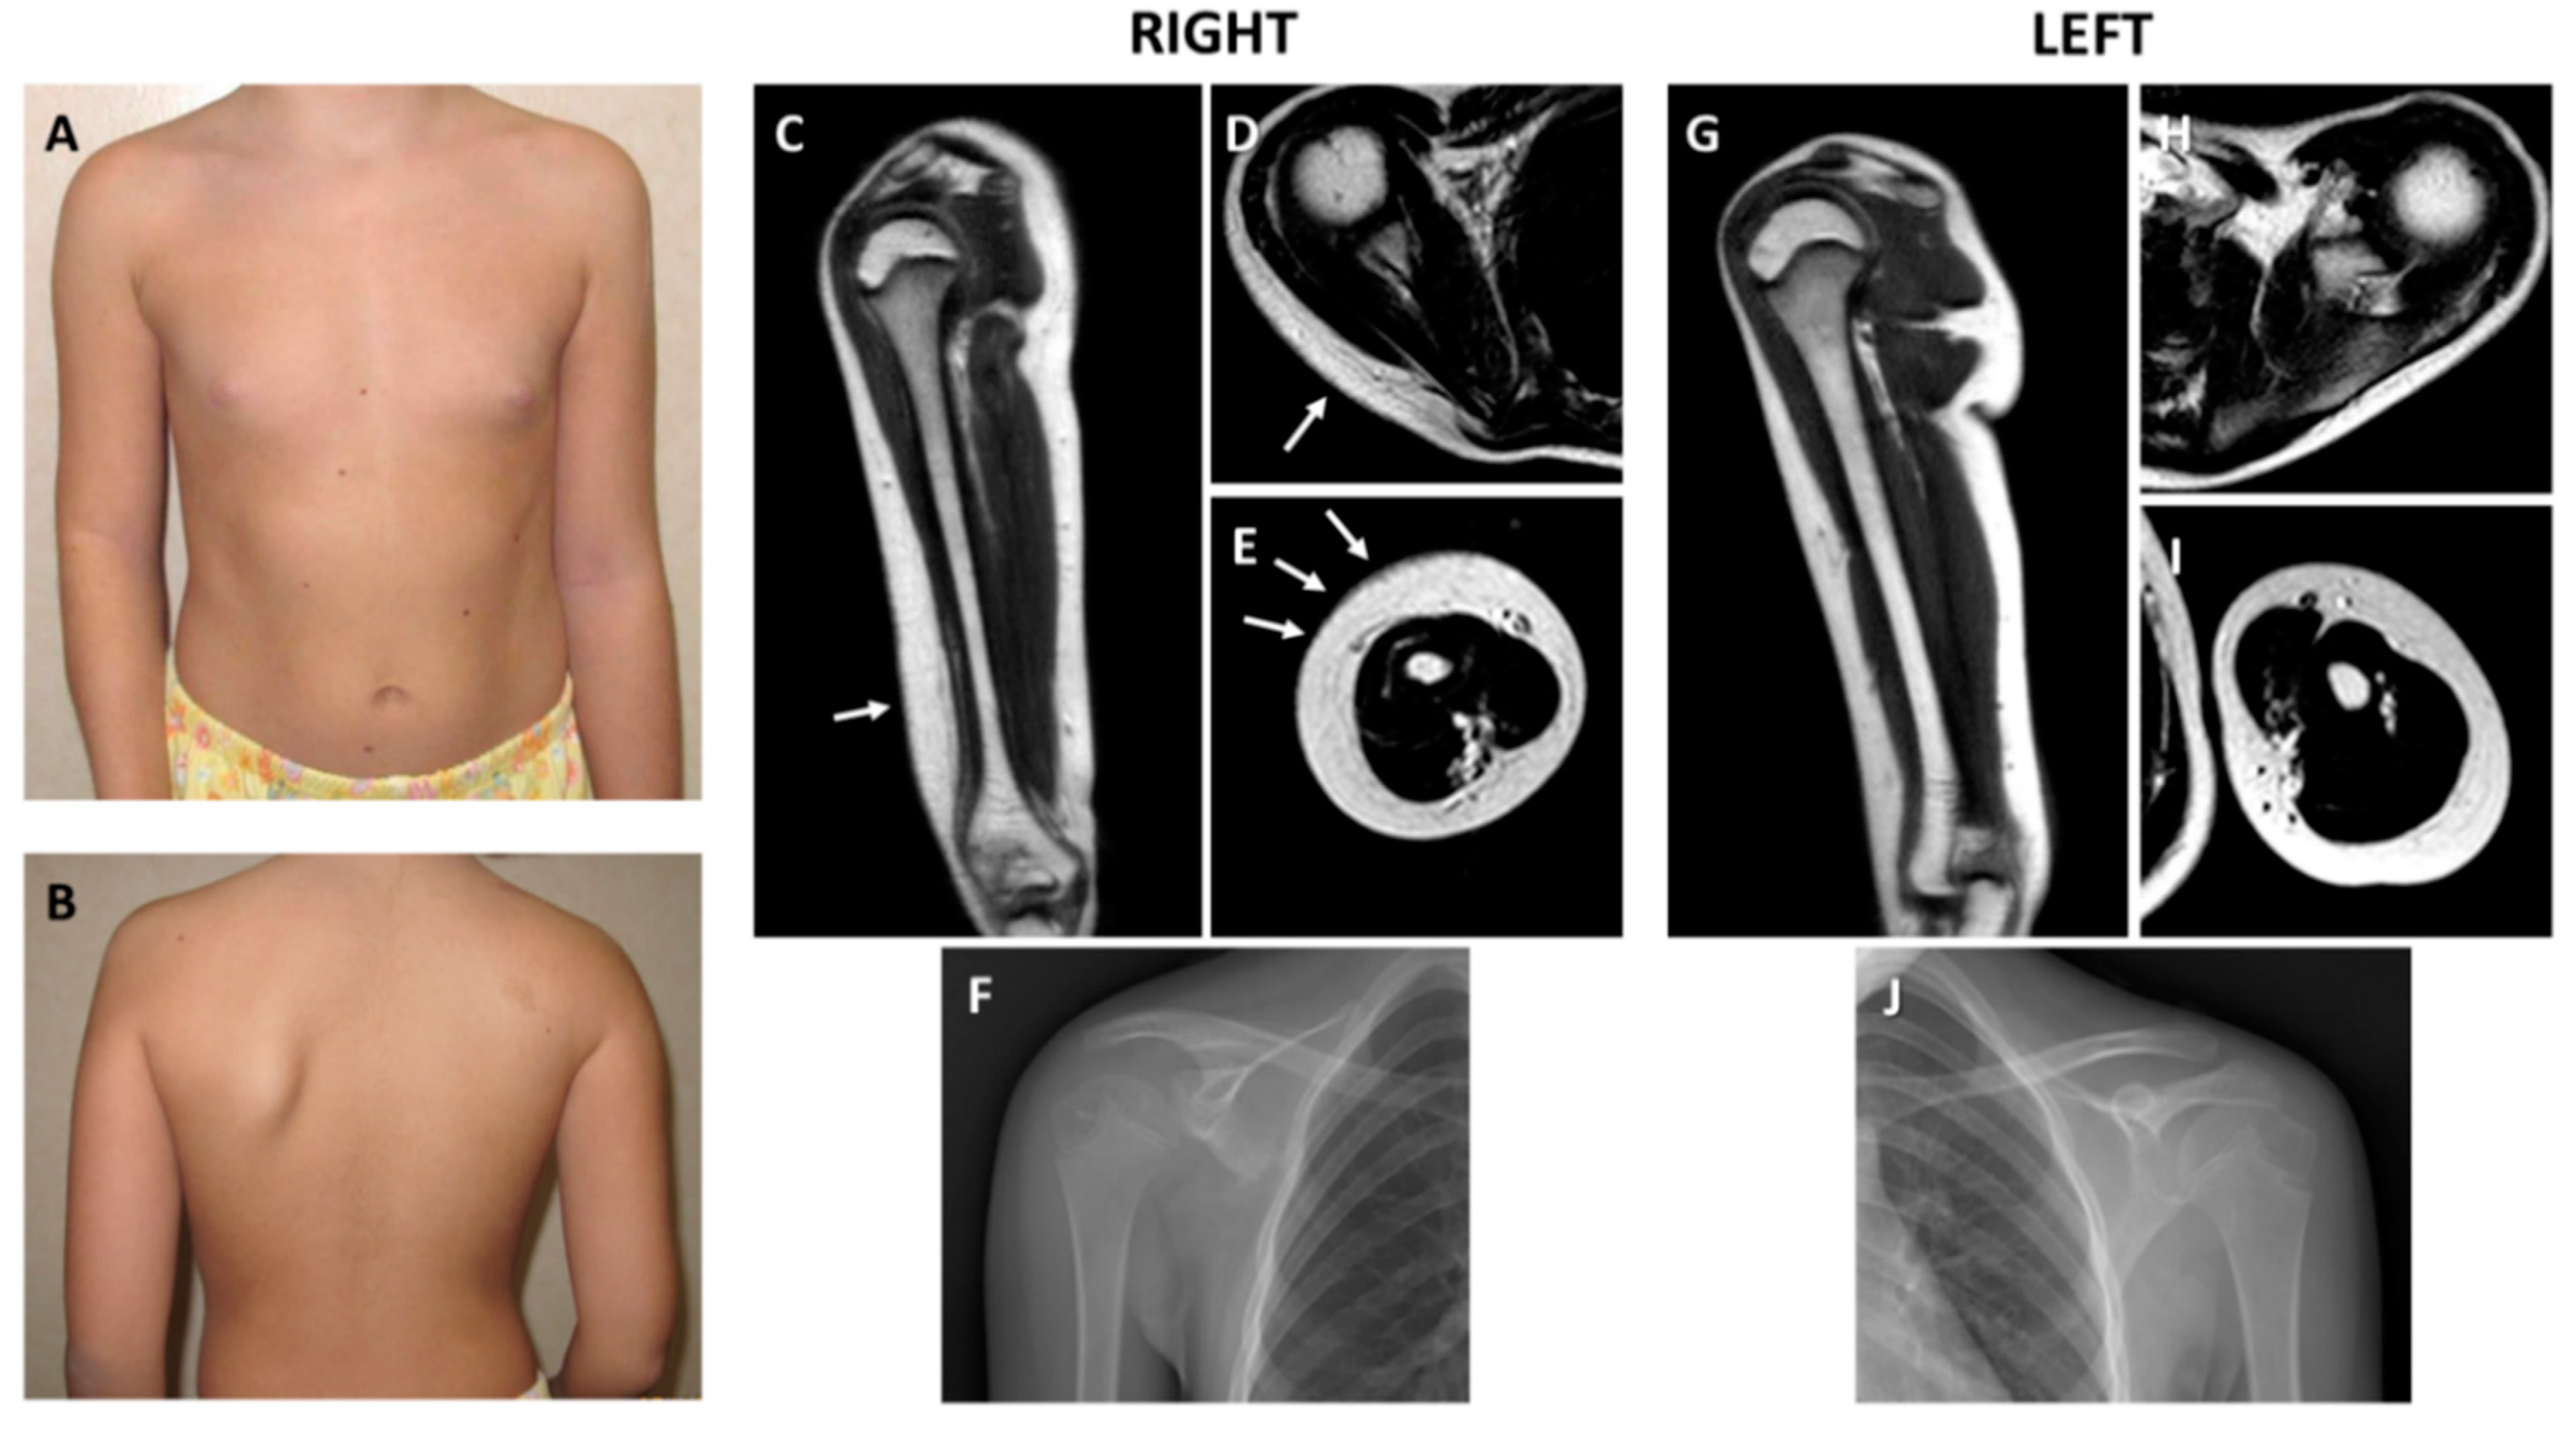

2.1. Clinical and Histological Findings